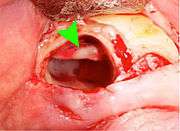

The procedure, depending on the depth of the impaction and angle of the tooth, is to create an incision in the mucosa of the mouth, remove bone of the mandible or maxilla adjacent the tooth, section the tooth and extract it in pieces. This can be completed under local anaesthetic, sedation or general anaesthetic.

Coronectomy

Coronectomy is a procedure used when the surgeon believes that there is a high risk of inferior alveolar nerve injury. After making the incision in the mucosa and removing bone adjacent the tooth, the crown is cut and removed with no attempt at removing the roots. It is indicated when there is no disease of the dental pulp or infection around the crown of the tooth and there is a high risk of inferior alveolar nerve injury.